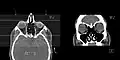

-

CT scan of the paranasal sinuses with coronal reconstruction (right) and axial planning data (left). -